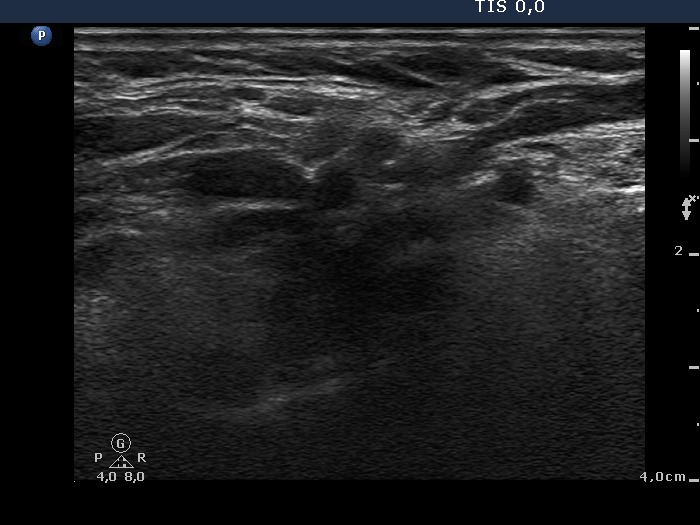

Papillary carcinoma - Case 2. (ultrasound picture 9)

Right side of the neck. There are multiple hypoechogenic lesions in the central part of the image.